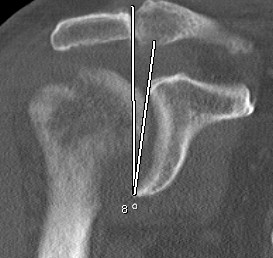

CT scan

Axial - assess glenoid bone stock / version

Centering guide wire passed

Depuy Synthes Delta Xtend

Center of inferior circle of glenoid

- metaglene needs to be positioned low to prevent inferior impingement and dislocation

- wire needs to angle perpendicular or slightly inferior / avoid superior tilt

- should exit scapula anteriorly about 3cm medial to glenoid